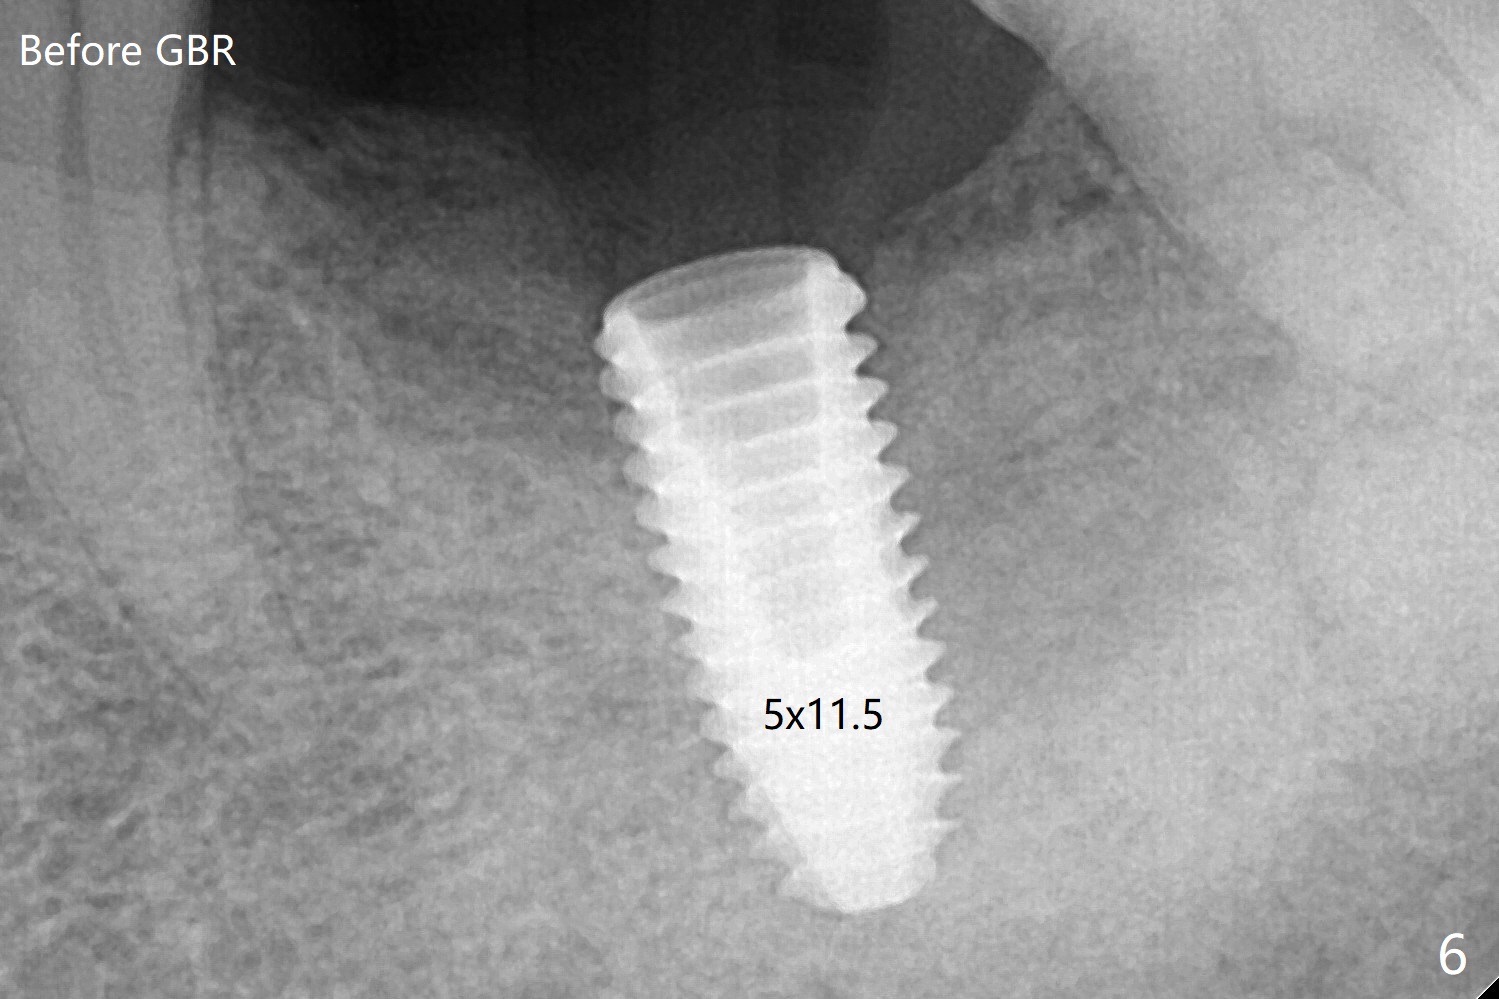

Note radiolucency around the implant (5x11.5 mm) before GBR (Fig.6). The bone density around the implant increases with distinct trabecular pattern consistent with stress 5 months post cementation (1 year postop, Fig.12).